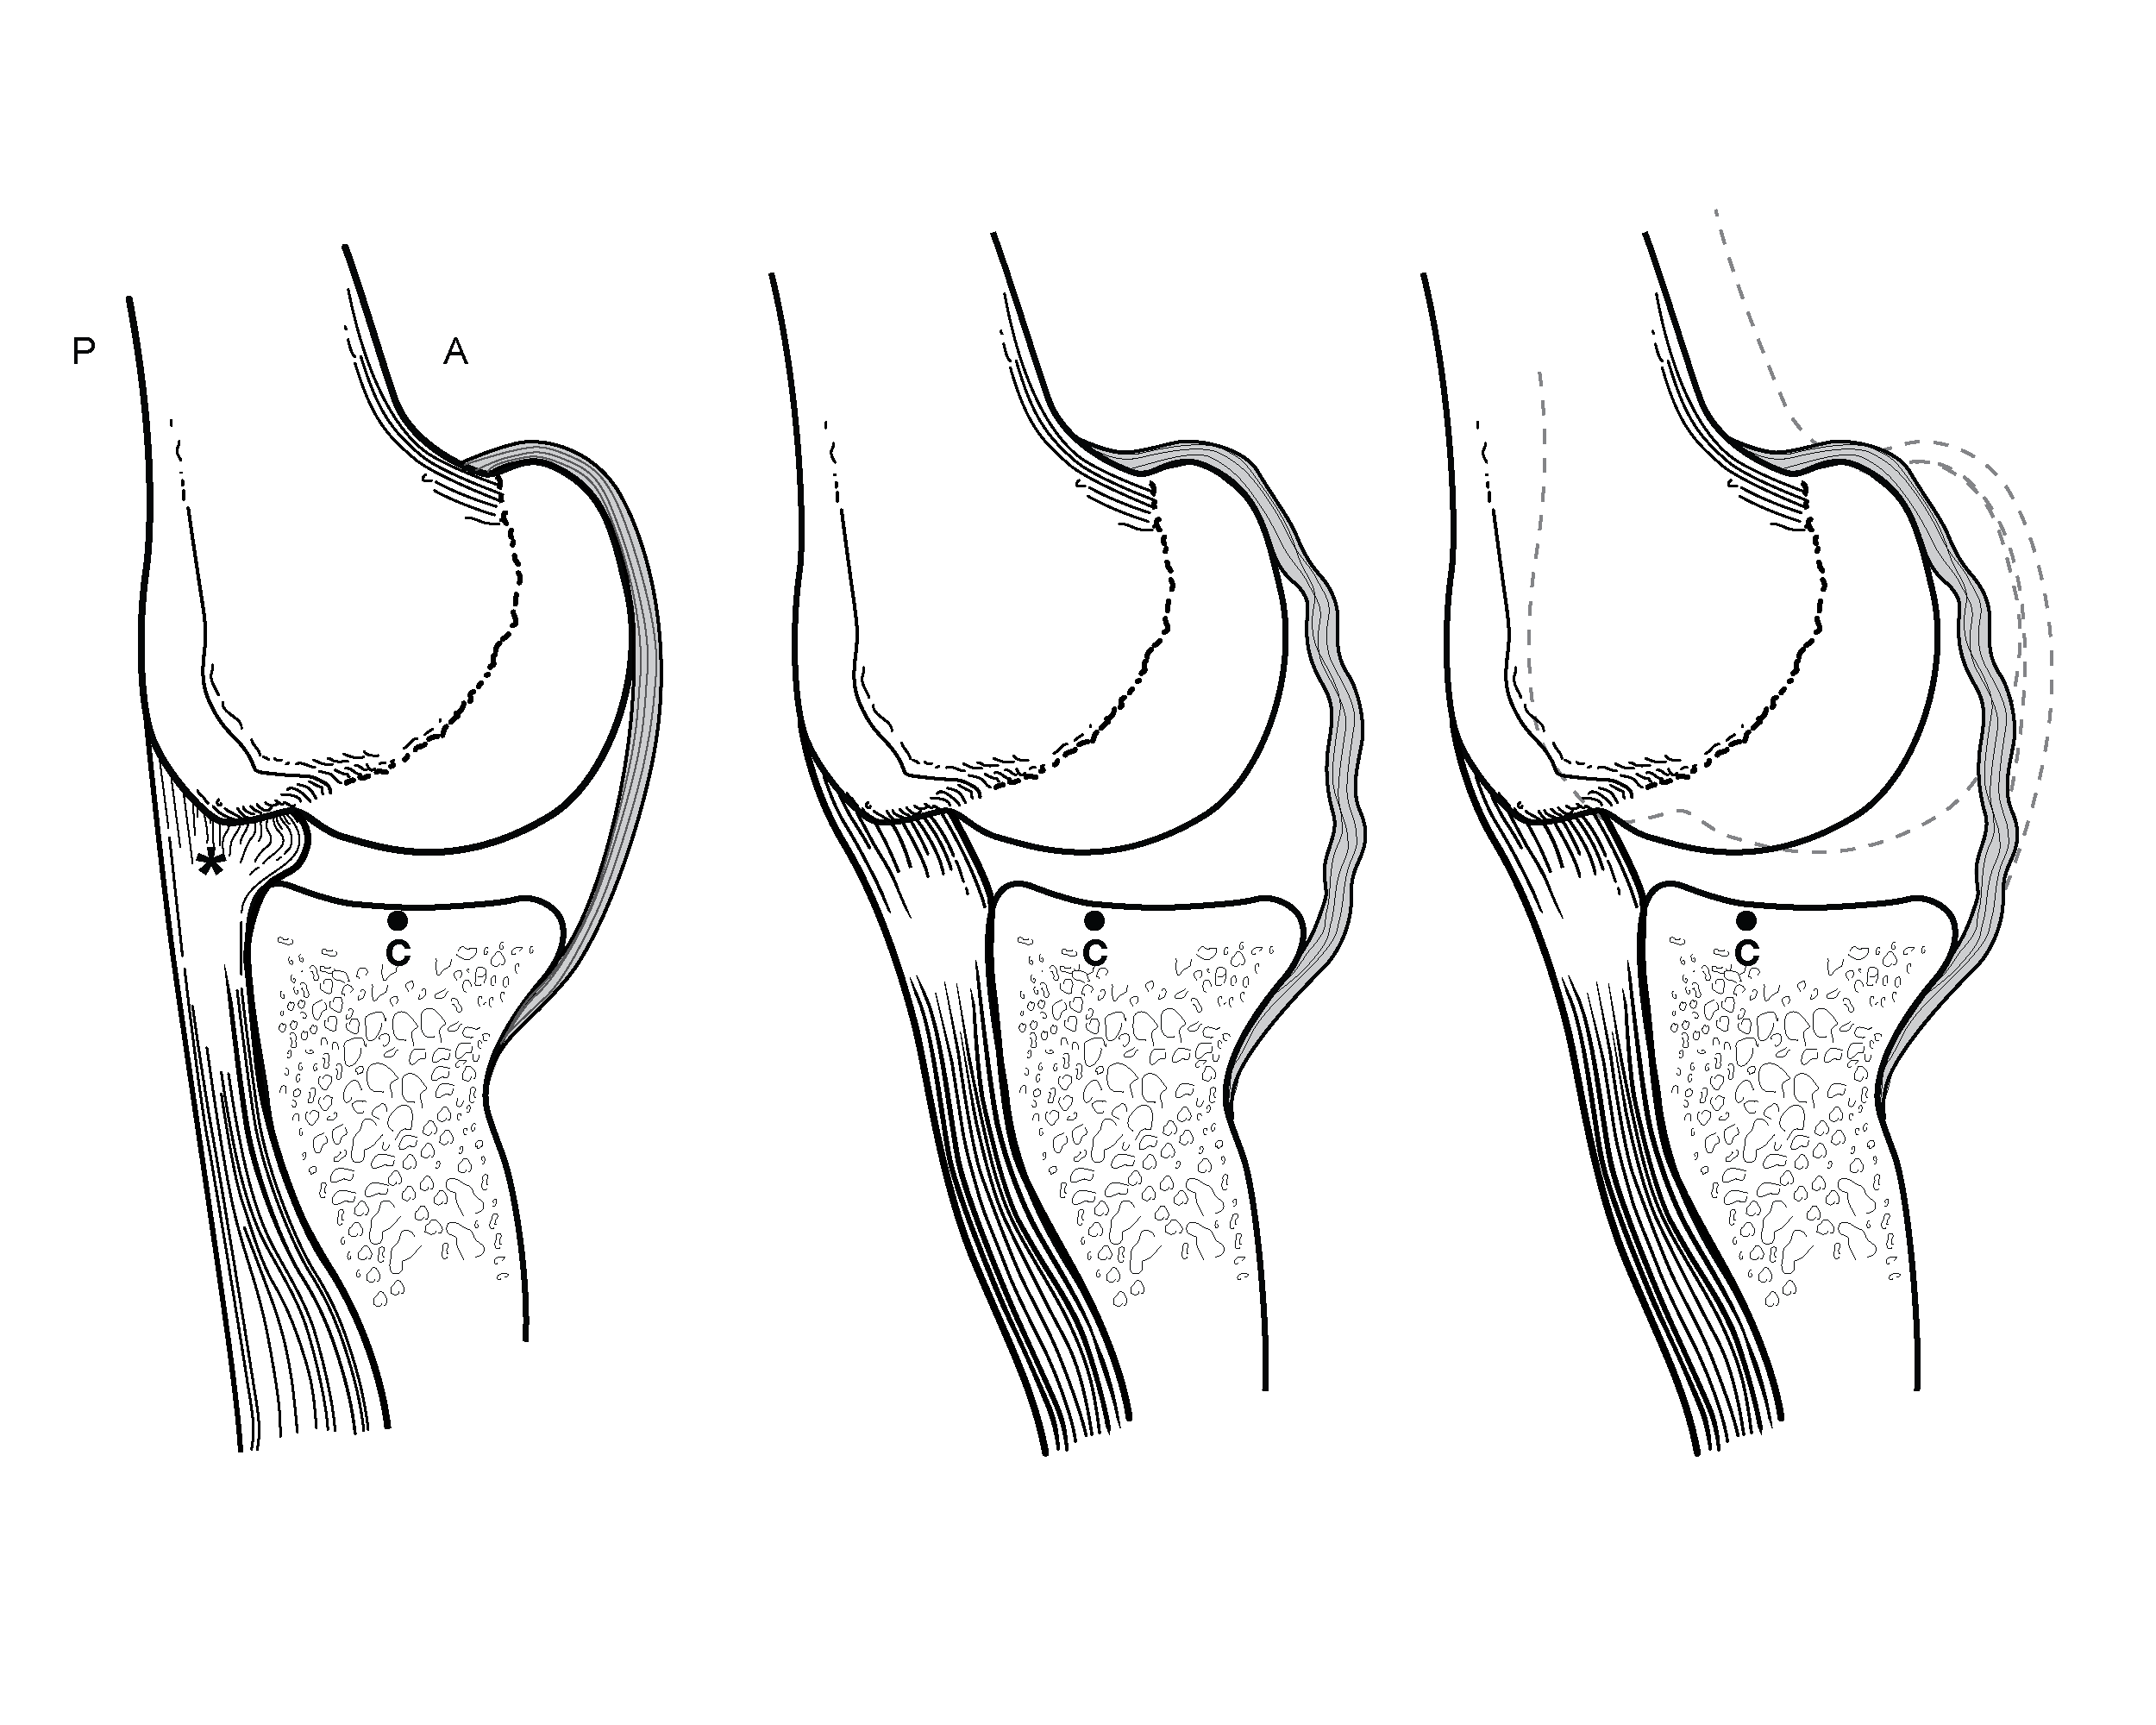

Surgical illustrations visually depict operative techniques, surgical anatomy, and complex procedures. They are created with high anatomical accuracy and serve as a visual bridge between complex surgical knowledge and learners, clinicians, or patients.